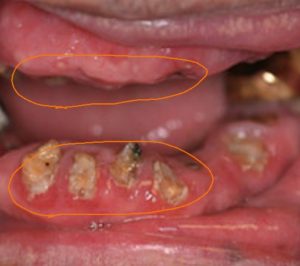

援助や介護を必要とする高齢者本人、介護をする側の人にとって残根状態の歯(根だけ残って頭がない歯)は"無い歯"として認識され、歯磨きが行き届かないのも現実です。

特に上の歯はパッと見歯はありません・・・

根だけの歯には細菌が溜まりやすく、誤嚥性肺炎の危険性が高まることになります。

20本歯が残っていても、その歯が原因で病気になる可能性もあるということです。

残根だけでなく、複雑な補綴物が入っている口腔内は高齢者や介護者にとって歯磨きしにくく、歯垢(細菌の塊)が残りやすい・・・